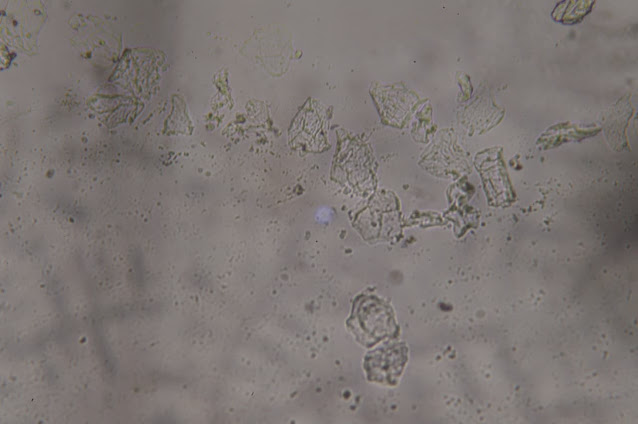

ここにあるいくつかの結晶は、もしかしたらショ糖かもしれません。しかし、ここには折り目があります。別のものを見てみましょう。こちらの方が目を引きますね。

ご覧のように、この写真は倍率を下げて撮影しているので、遠くから観察したときの遠近感がよくわかります。しかし、これは、例えば、これらの組織は、酸化グラフェンと同じような特性を持っています。続けましょう。

リカルド・デルガド: はい。ここでは、もう少し小さく、つまり倍率を下げて見ています。

ここでは、その小さなハンカチの「破片」もたくさん見ることができます。もう少し拡大してみました。

サンプルは左が昨年のあのVaxigripのインフルエンザワクチン、20209月・10月のものです。そして右は、別のコンデンサーで、科学文献に描かれているような酸化グラフェンを見ることができます。つまり、左のサンプルに見られるように、ひだがあり、いくつかの層が重なっています。右の写真と同じような特徴があり、ひだやエッジが折り重なっているのがわかります。非常によく似ています。このナノ材料を扱っている人や、光学顕微鏡や電子顕微鏡で見たことがある人に聞いてみると、「これも酸化グラフェンだ」と言われました。どうですか?これが20209月・10月のインフルエンザワクチン「Vaxigrip」です。